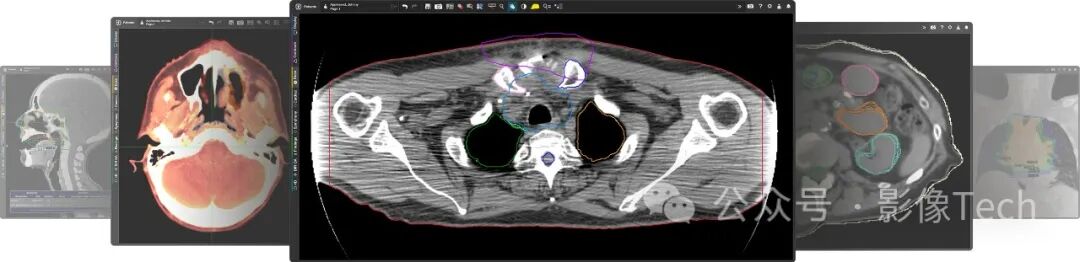

公司旨在为放射肿瘤学、核医学、放射学、介入放射学、分子、神经和心脏的成像提供创新的软件解决方案。公司到目前为止推出了MIM Maestro®、Contour ProtégéAI+™、MIM Encore®等软件。

GE医疗计划将MIM Software的解决方案整合到其先进的可视化产品中,以支持以AI技术为基础的影像分割、轮廓绘制、放射剂量测定分析等服务。这一整合旨在帮助医疗机构更好地为患者提供医学影像,同时在放射学、分子成像和放射肿瘤学等领域推动创新。